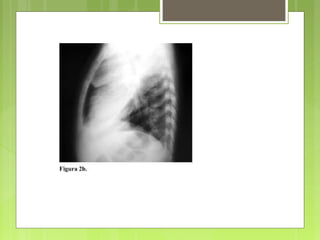

derecha; se practica una Rx tórax (AP y lateral) (

figura 2a y 2b) y el paciente es trasladado a la unidad

En la figura 2a y 2b se observa

condensación en los LSD, lóbulo medio

y lóbulo inferior derecho, además de

derrame pleural laminar derecho.